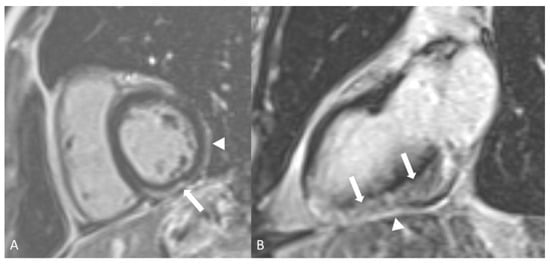

- Dennert, R.M.; van Paassen, P.; Schalla, S.; Kuznetsova, T.; Alzand, B.S.; Staessen, J.A.; Velthuis, S.; Crijns, H.J.; Tervaert, J.W.C.; Heymans, S. Cardiac involvement in Churg-Strauss syndrome. Arthritis Rheum. 2010, 62, 627–634. [Google Scholar] [CrossRef]